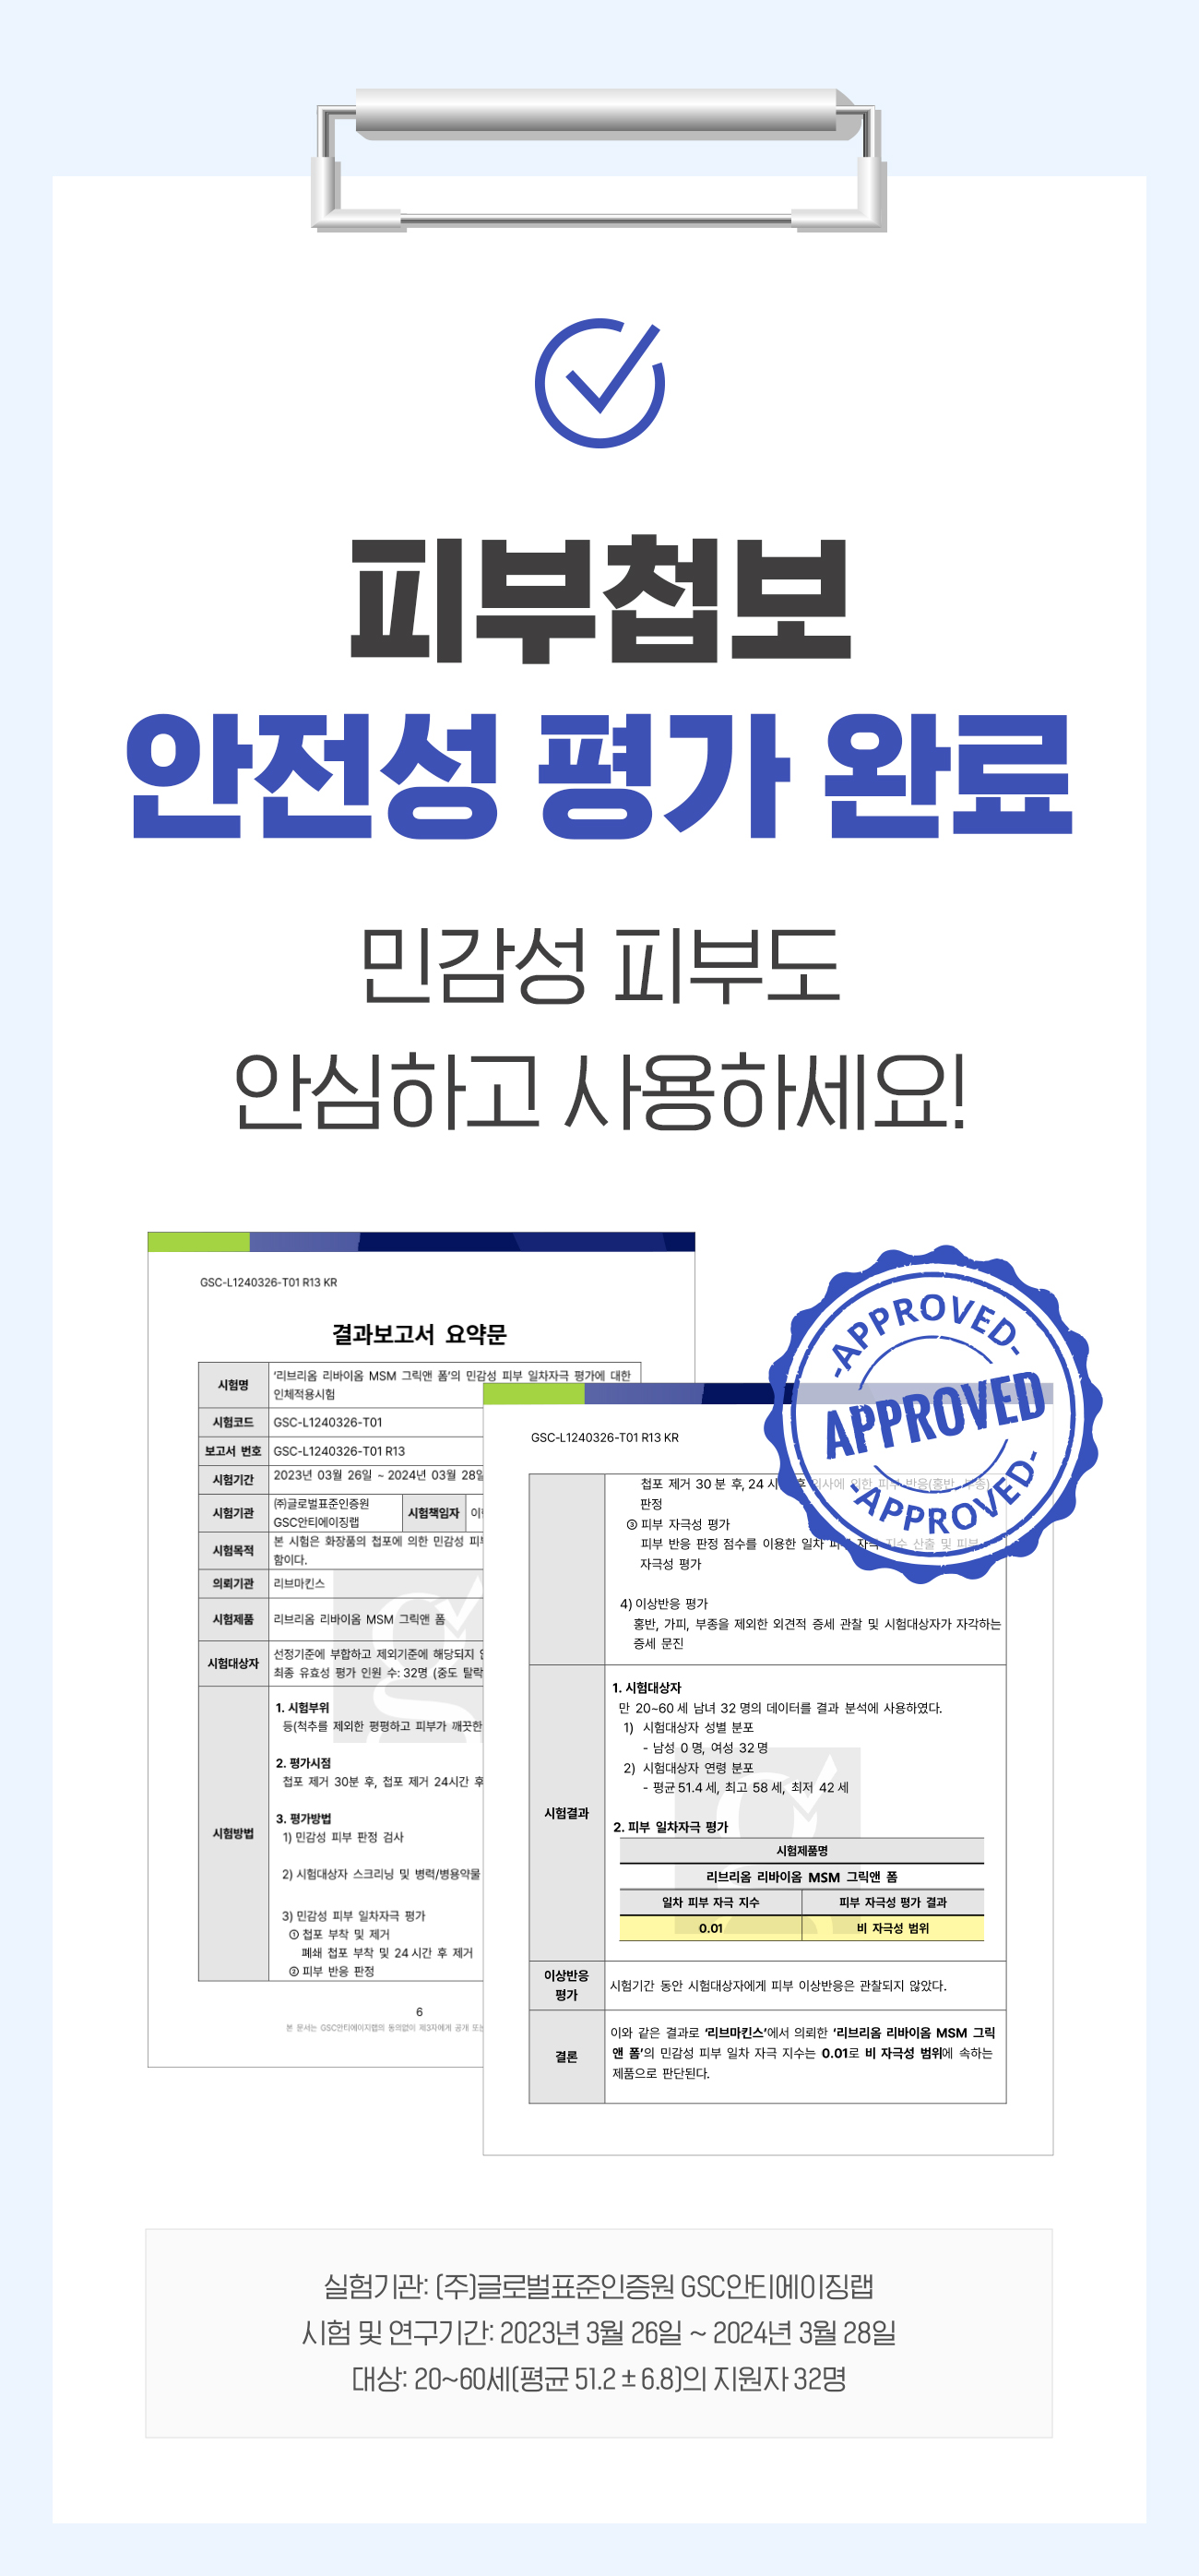

Q. 민감한 피부도 사용할 수 있나요?

A. 민감성 피부 테스트 완료로 민감성 피부도 안심하시고 사용이 가능합니다. 하지만 개인차가 있을 수 있으니 자극이 있을 경우 사용을 중지하시고 전문가와 상담하길 권장합니다.